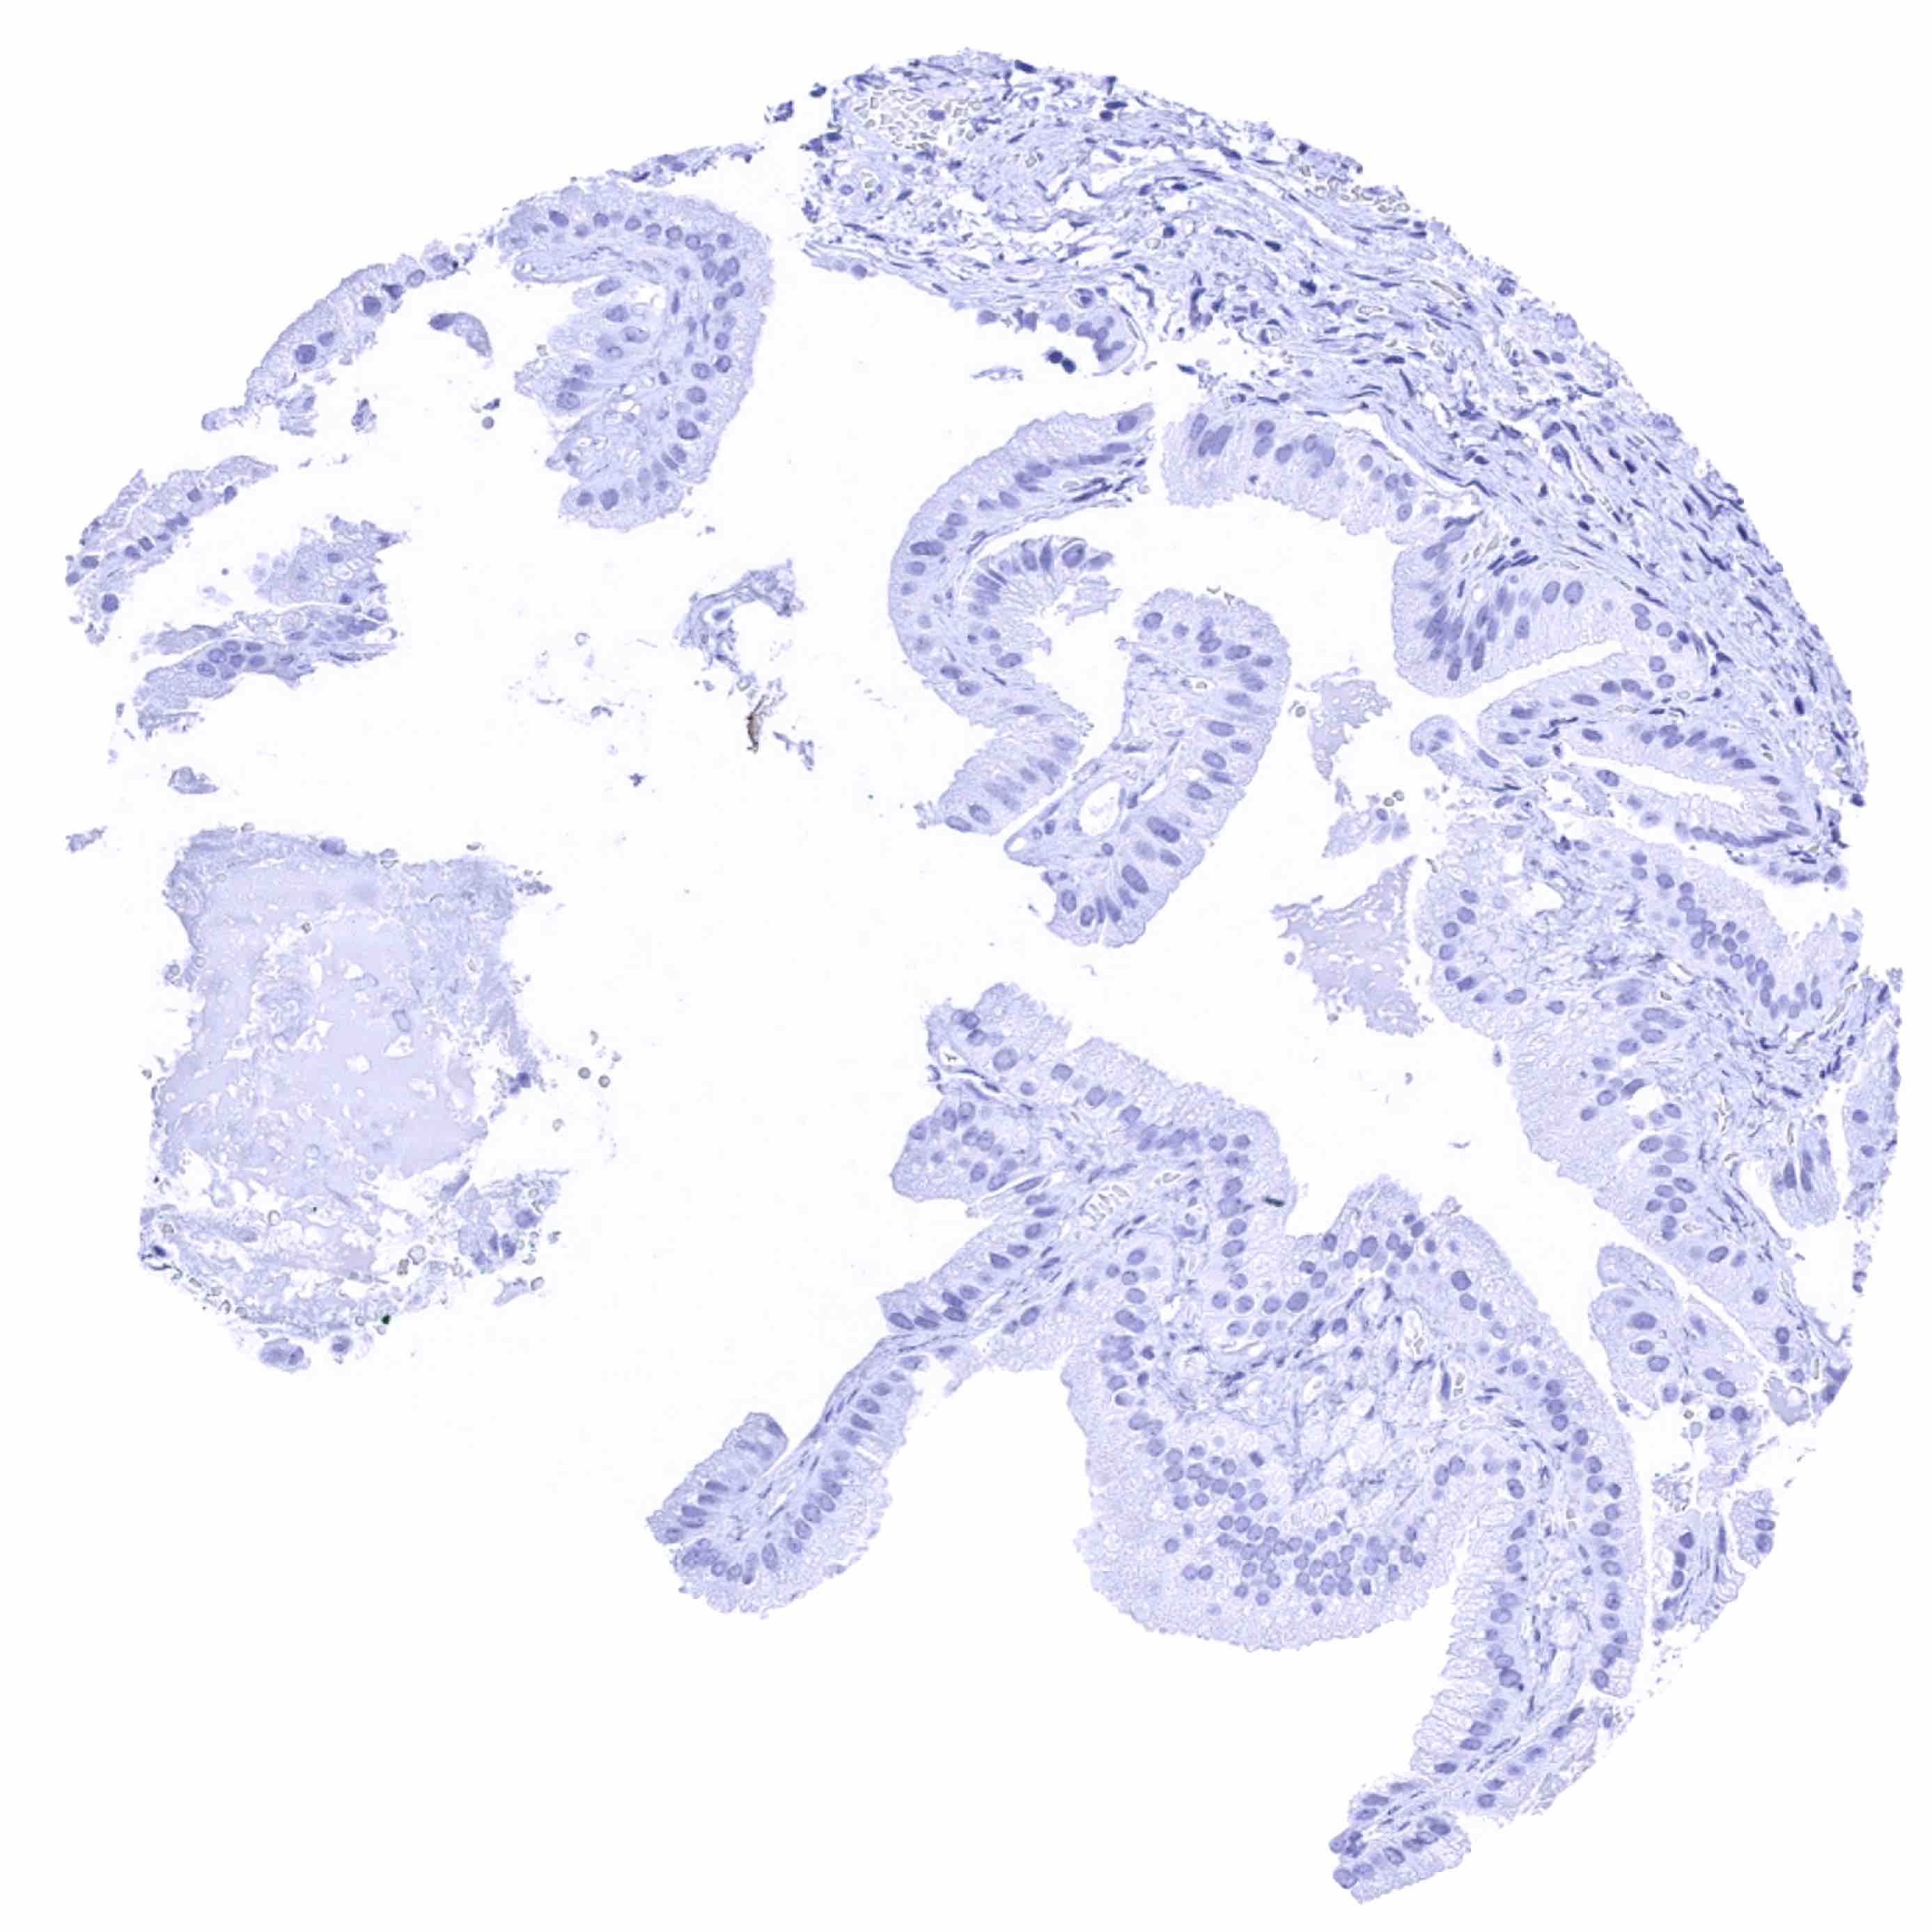

Uterus, endocervix